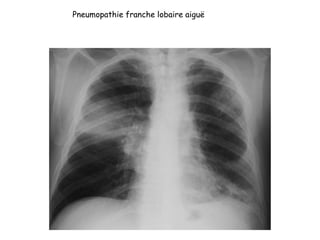

Pneumopathie franche lobaire aiguë